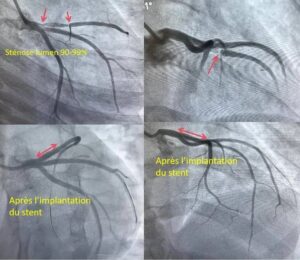

À Conakry, la 31ᵉ mission médicale chinoise œuvre en étroite collaboration avec les médecins de l’hôpital de l’amitié Sino-Guinéenne. Ensemble, ils unissent leurs compétences pour offrir des soins spécialisés aux patients atteints de maladies coronariennes.

Selon les responsables de l’établissement, cette coopération internationale représente bien plus qu’un partenariat médical : elle sauve des vies et ravive l’espoir au sein de nombreuses familles guinéennes.